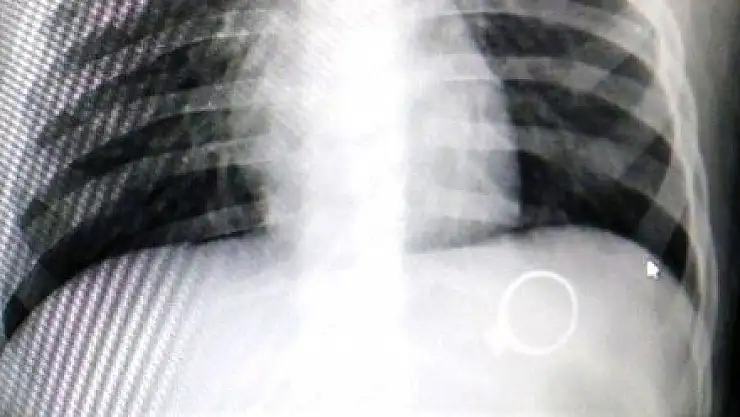

RÖNTGENDE BELLİ OLDU

Çocuk Cerrahisi Uzmanı Op.Dr. Mahmut Aluç, çekilen röntgende yüzüğün midede olduğunu belirlediklerini ifade ederek, "Hastamız 1 buçuk yaşında. Bundan 6 gün önce bize yüzük yutma şikayeti ile başvurdu. İlk çektiğimiz grafide yüzüğün mide de olduğunu saptadık ve aileyi bilgilendirdikten sonra rutin prosedürlerinin gereği beklemeye başladık. 6 gün sonra spontane olarak yüzüğün kendisi çıktı. Bu tür hastalarla oldukça sık karşılaşıyoruz. Rutin olarak şöyle bir kural vardır, çocuk ağzına aldığı her şeyi yutabilir. Özellikle küçük çocuklar cisimleri tanımak için elleriyle dokunduktan sonra genellikle ağızlarına alırlar. Bu yutulan cisimler toplu iğne olabilir, çengelli iğne olabilir, para olabilir" dedi.